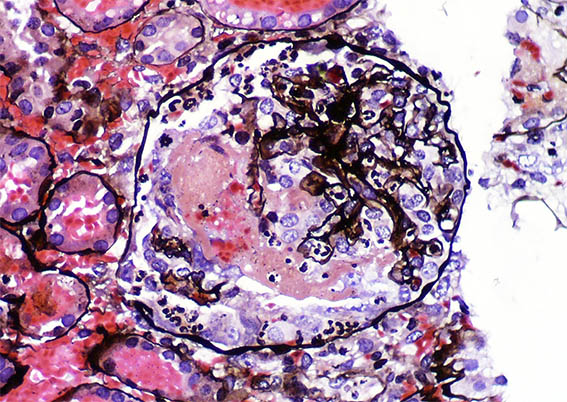

Figure 10. Masson's trichrome stain, X400.

Figure 11. Methenamine-silver stain,

X400.